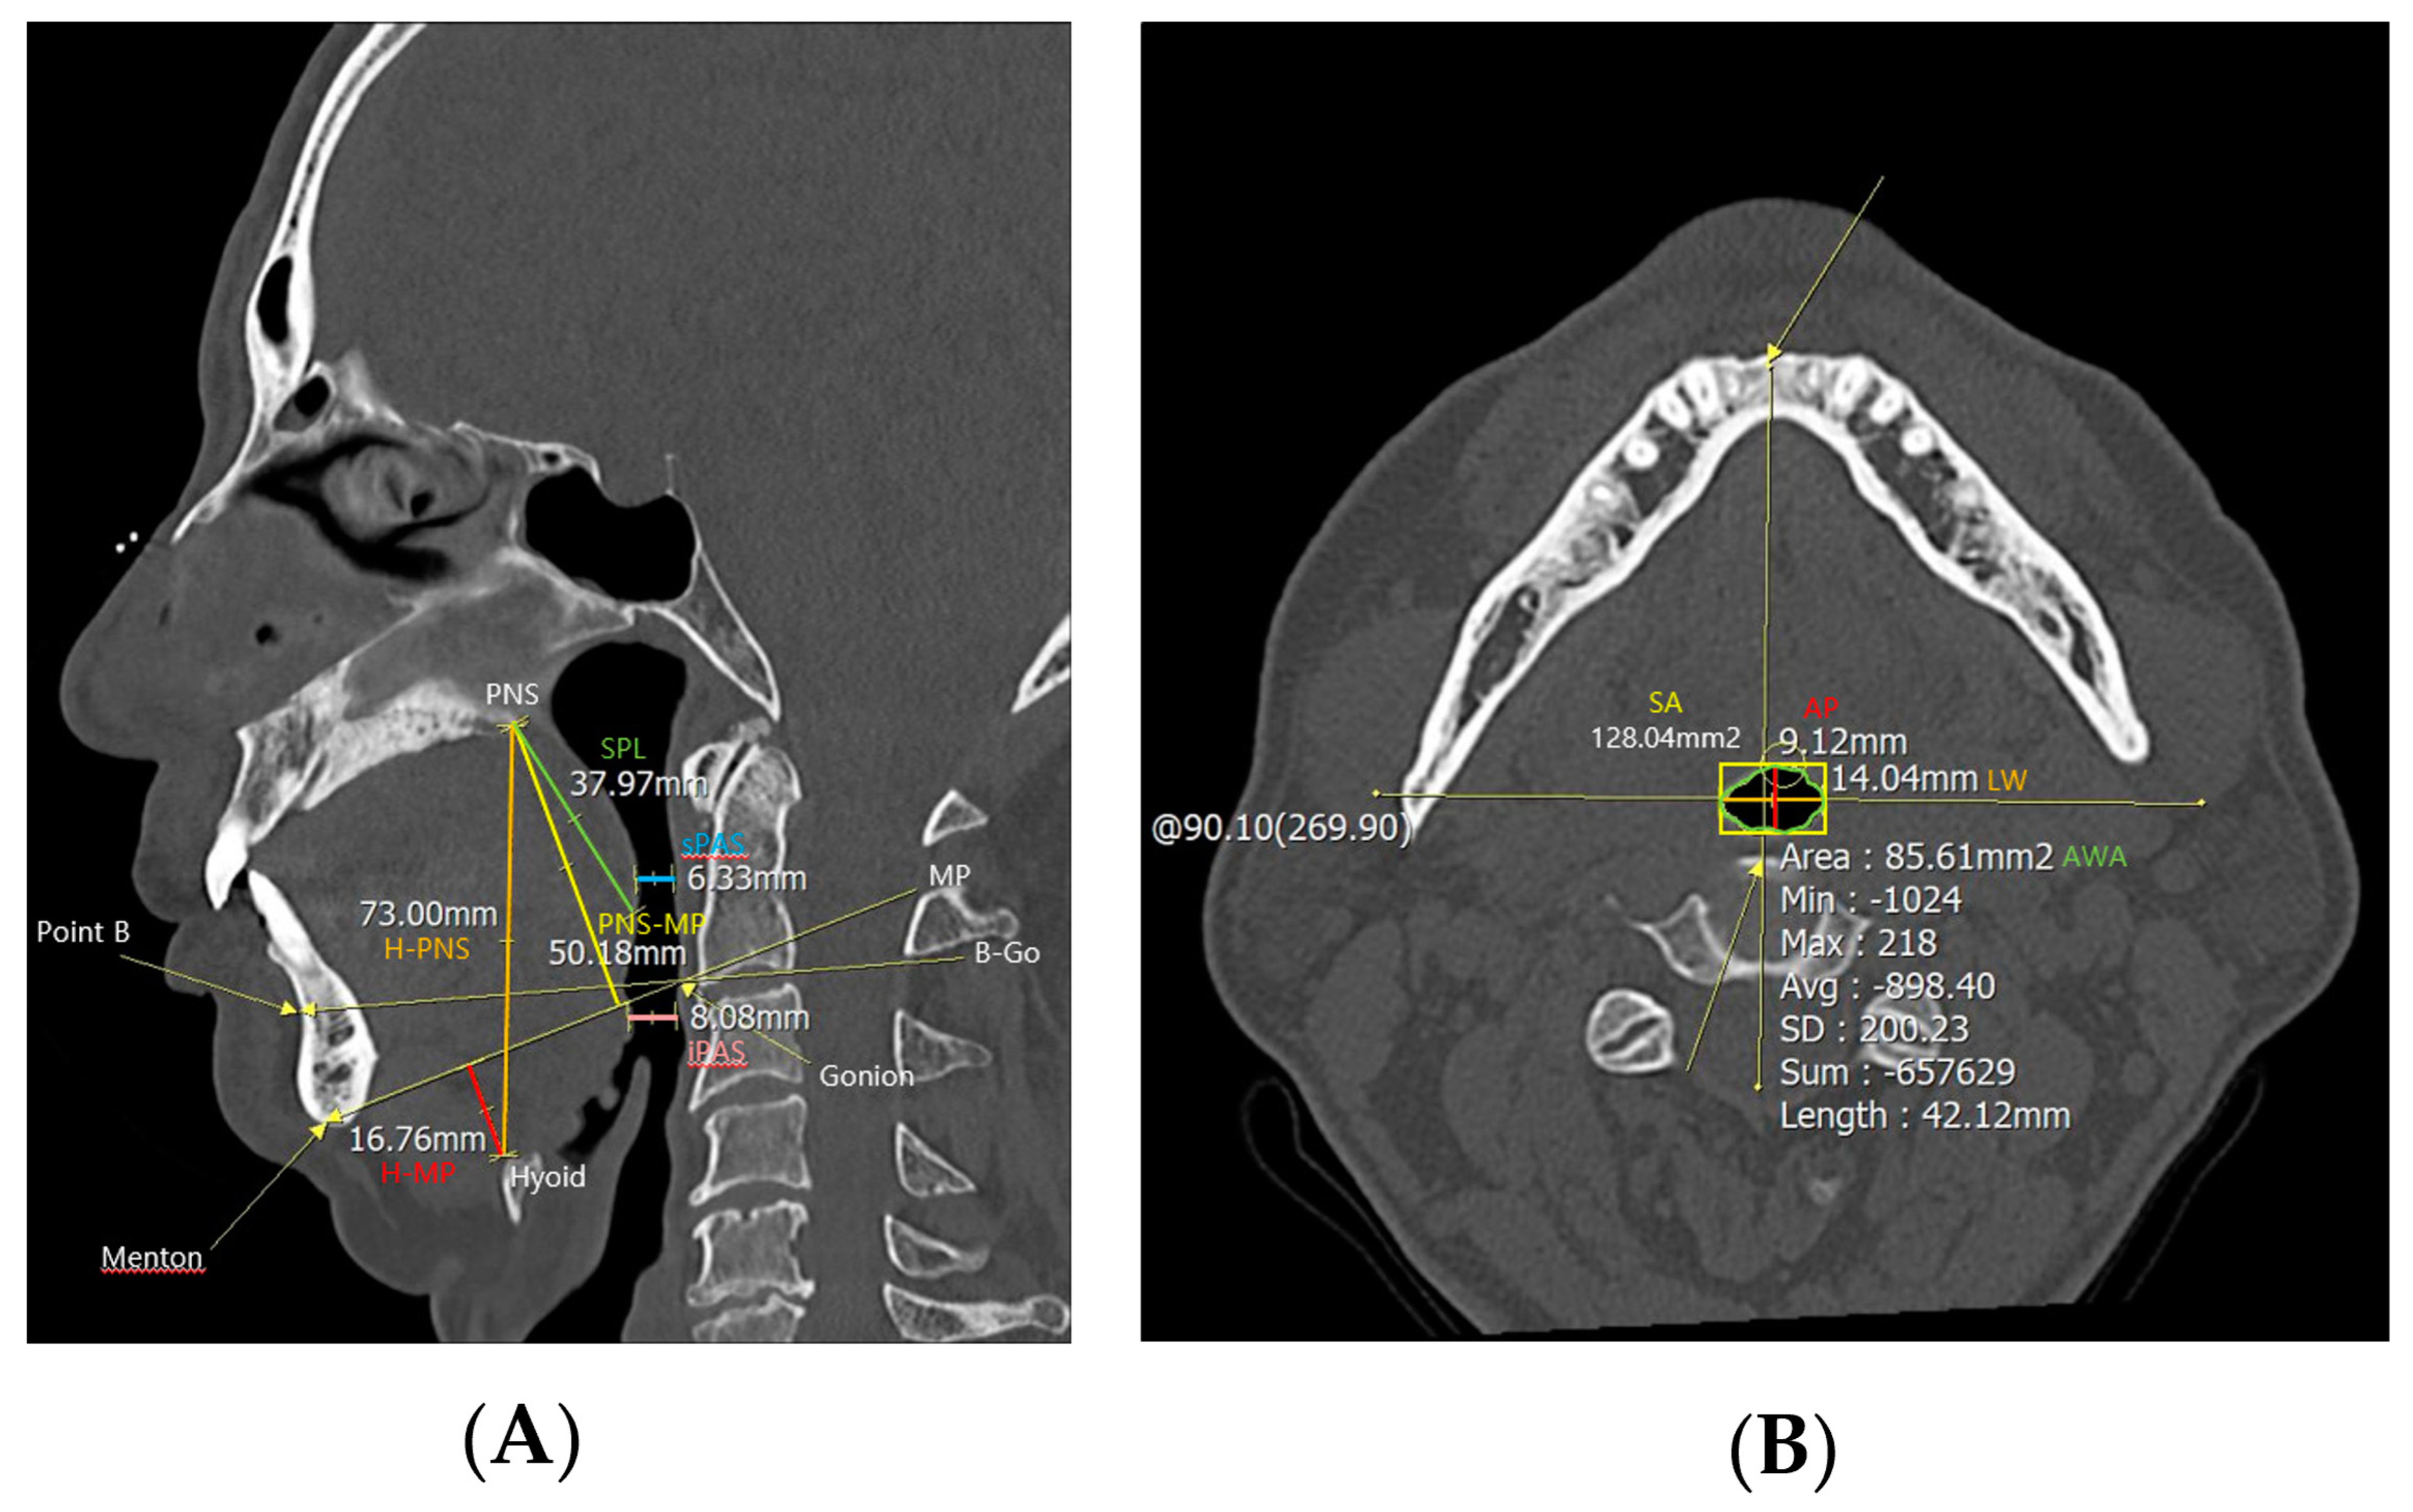

PNS CT was performed to examine anatomical abnormalities of the upper airway. In the midsagittal view of CT, cephalometric parameters such as H-PNS (distance between the hyoid bone and posterior nasal spine), posterior nasal spine-mandibular plane (distance between posterior nasal spine and mandibular plane, PNS-MP), H-MP (distance between the hyoid bone and mandibular plane), superior posterior airway space (distance between the posterior wall of the pharynx and the soft palate parallel to the B-Go plane, sPAS), inferior posterior airway space (distance between the posterior wall of the pharynx and the base of the tongue parallel to the B-Go plane, iPAS), and SPL were measured (Figure 1). And in the axial view of computed tomography, the anterior–posterior width (AP), lateral width (LW), square area (SA), and airway cross-sectional area (AWA) of the airway were measured at the level of the anterior–inferior corner of the second cervical vertebra [10].

Figure 1. Cephalometric parameters measured using PNS CT. H−PNS, PNS−MP, H−MP, sPAS, iPAS, and SPL were measured in (A) the midsagittal view of the PNS CT, and AP, LW, SA, and AWA were measured in (B) the axial view. Abbreviations: H−PNS, hyoid–posterior nasal spine; P–MP, posterior nasal spine–mandibular plane; H–MP, hyoid–mandibular plane; sPAS, superior posterior airway space; iPAS, inferior posterior airway space; SPL, soft palate length; AP, anterior–posterior width; LW, lateral width; SA, square area; AWA, airway cross–sectional area.